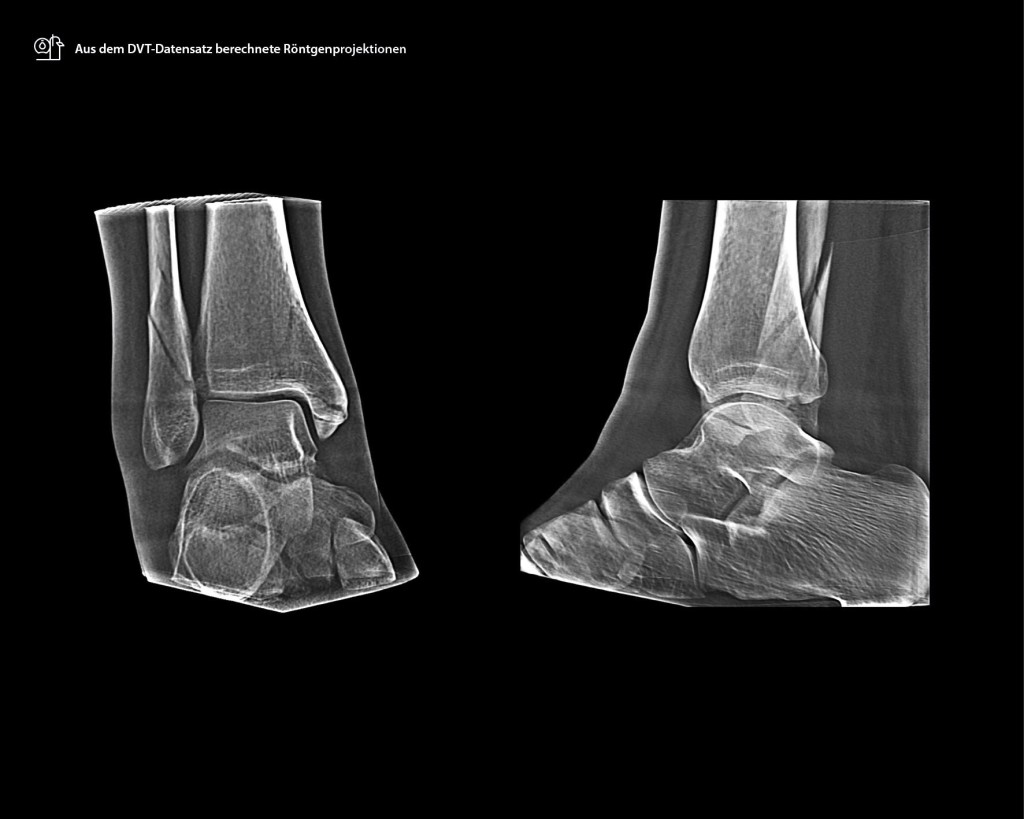

Die Untersuchung mit dem SCS DVT zeigte einen gravierenderen Befund, der auch Einfluss auf die Indikation des operativen Verfahrens hat. Es bestätigte sich die Mehrfragmentfraktur der distalen Fibula, sowie die Innenknöchelfraktur. Entscheidend ist aber die Möglichkeit der exakten Beurteilung der dorsalen Frakturen der Tibia. Diese sind aufgrund der Summation im konventionellen Röntgen nicht zu erkennen gewesen. Neben der Fraktur des Volkmann-Dreiecks mit entsprechender Instabilität der dorsalen Syndesmose zeigt sich eine Impression eines Gelenkfragmentes und eine Fraktur der dorsomedialen Tibia (Abb. 2–4). Die gesamte effektive Strahlendosis betrug 1,5 μSv für das 2-D-Röntgen + 1,4 μSv für das DVT im SULD-Protokoll, insgesamt 2,9 μSv. Bei einer konventionellen CT-Untersuchung wären es 1,5 μSv + 21,4 μSv = 22,9 μSv gewesen. Bei einer sofortigen Untersuchung mit dem DVT hätte die Dosis 1,4 μSv betragen. Aufgrund dieser komplexen Verletzungsmuster bestand die Indikation zur Operation in Bauchlage zur Versorgung der dorsalen Frakturen der Tibia und Fibula über einen dorsolateralen Zugang sowie perkutan zur Verschraubung des medialen Malleolus.